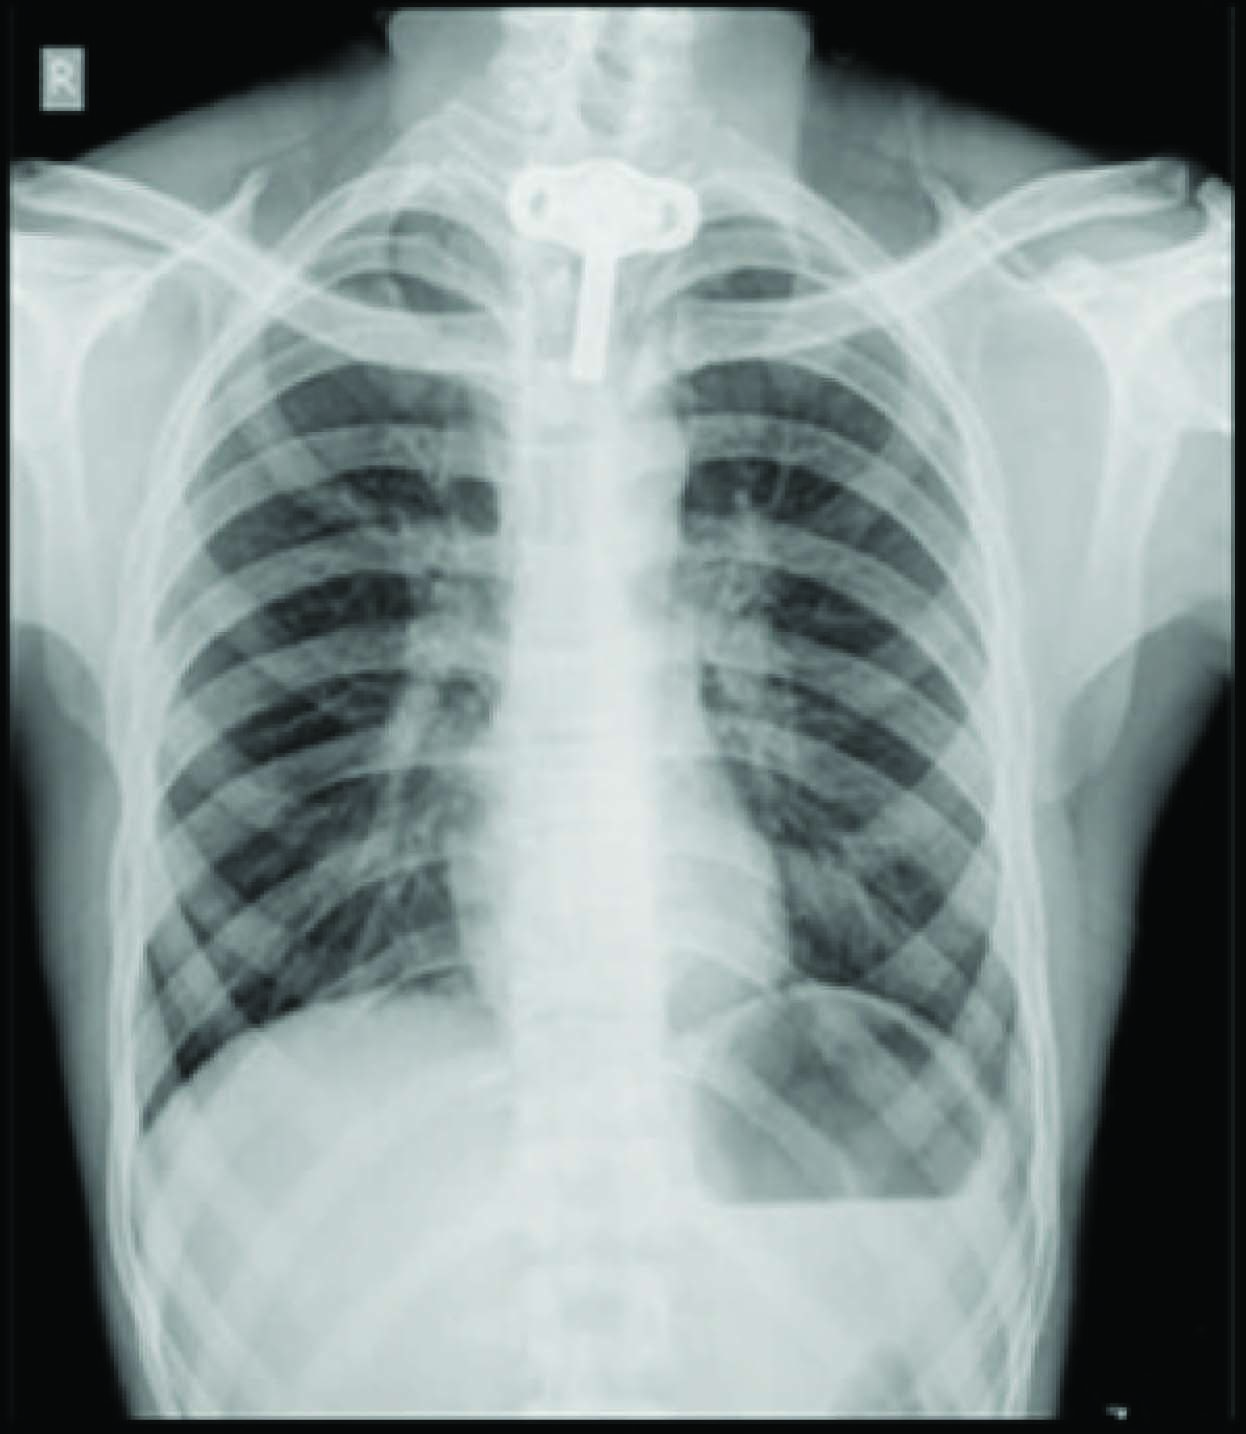

On Examination: Patient was averagely built and well nourished, conscious, comfortable, and could speak clearly by closing tracheostomy tube [Table/Fig-1]. Patient was on nasogastric tube no.14 in-situ. On examination his vital parameters were pulse rate was 78/minute, blood pressure 110/74mmhg and respiratory rate 18/minute. His Spo2 was maintained 100% on room air on auscultation of lungs, bilateral air entry was equal and no added sounds were noted. Other systemic examination findings were within the physiological normal limit. Patient MPC was grade I. Chest X-ray showed the metal tracheostomy tube in-situ with sub-glottic stenosis above tracheostomy tube more evident in lateral view [Table/Fig-2,3].

Chest x-ray showing level of tracheostomy tube